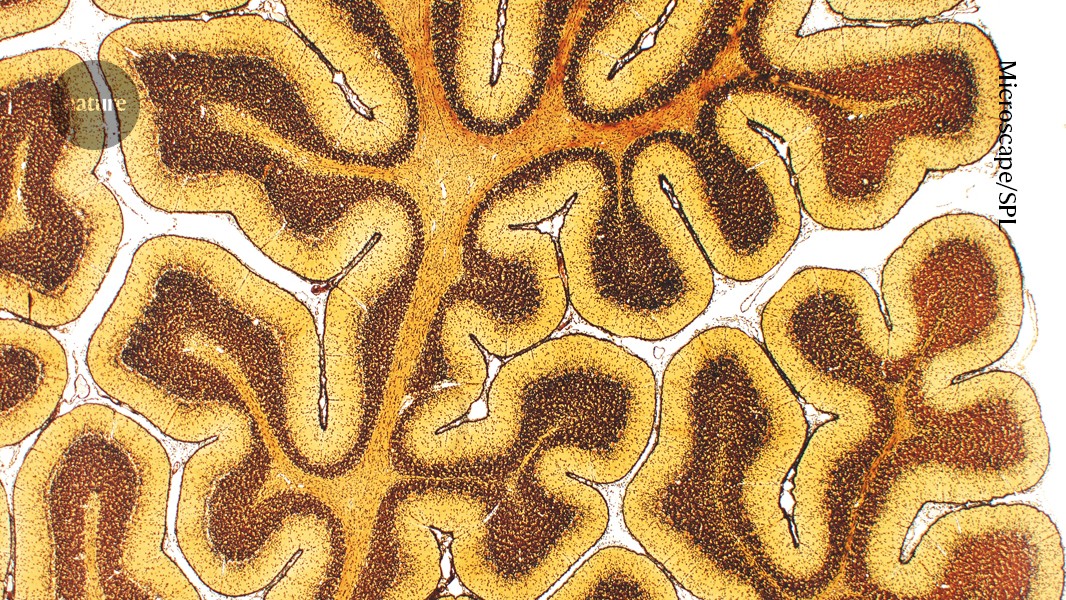

The regions of the brain that act in concert change as a person matures. Credit: Microscape/SPL